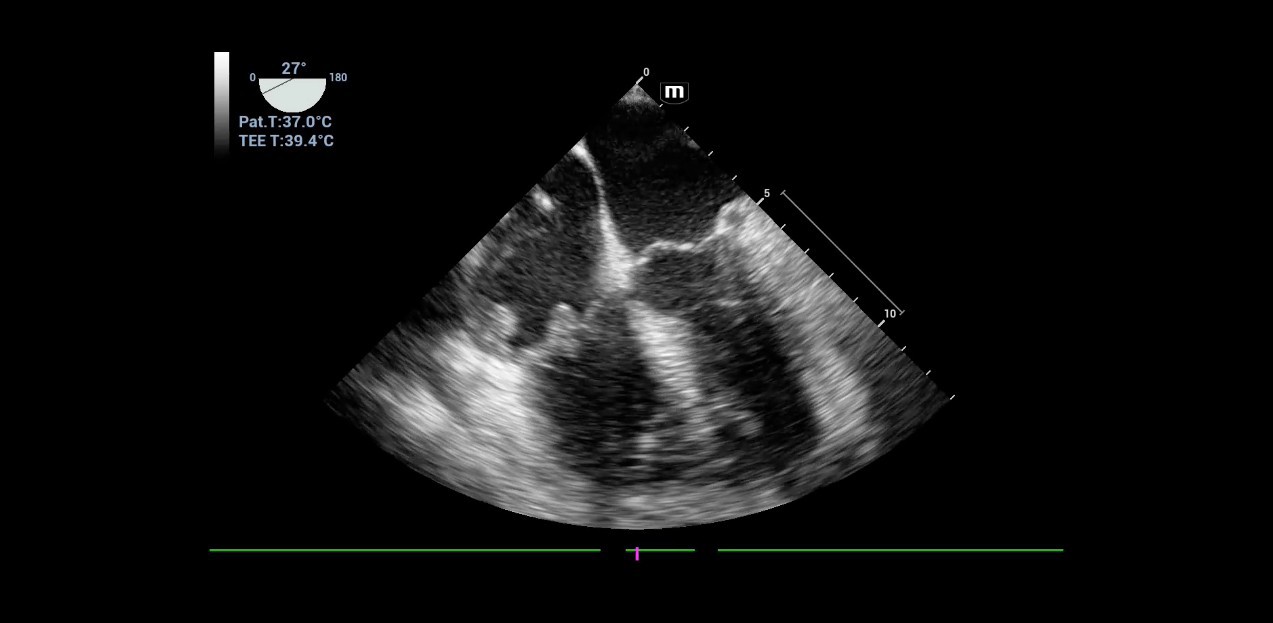

When working in an intensive care unit, obtaining a quick overview of a patient's health status is crucial. Sonography can non-invasively image multiple entities, some of which may be critical, in real-time. However, using this technology requires equipment that offers high flexibility without compromising image quality. For his department, specialized intensive care physician Dr. Armin Seibel relies on the high-end color Doppler ultrasound device Resona I9 from Mindray, which offers exceptional image quality, multifunctionality, and a long battery life.

Dr. Seibel chose Resona I9 for various reasons. First, the high-end device offers excellent image quality with high resolution, as well as focused examination techniques that facilitate diagnosis. For instance, he frequently uses contrast-enhanced ultrasound (CEUS) to clarify uncertain findings.